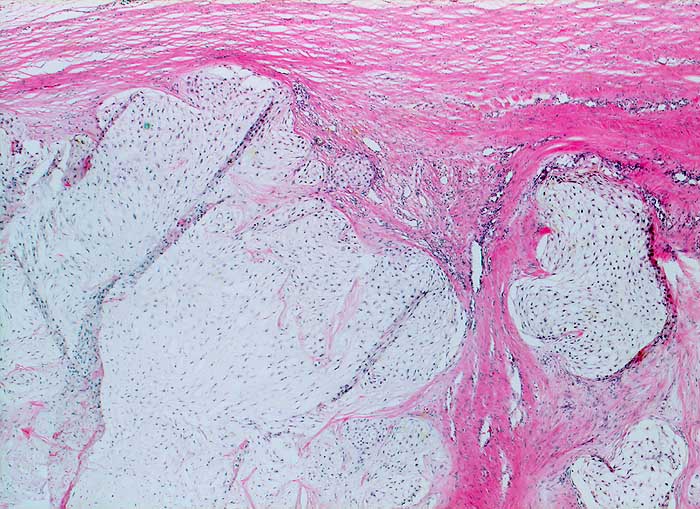

Der lobulierte chondroid differenzierte Tumor infiltriert die Weichteile der Thoraxwand. Das Sarkom ist deutlich zellreicher als normaler Knorpel vor allem in den Randpartien der Lobuli.

Makroskopischer Befund des Thoraxwandteilresektates: halbkugeliger Tumor (7,5x7x3,6cm). Auf Schnitt findet sich

ein gallertiger, teils knorpeliger Tumor mit Nekrosen und Einblutungen. Tumor durch die beiden mittleren Rippen durchtretend.